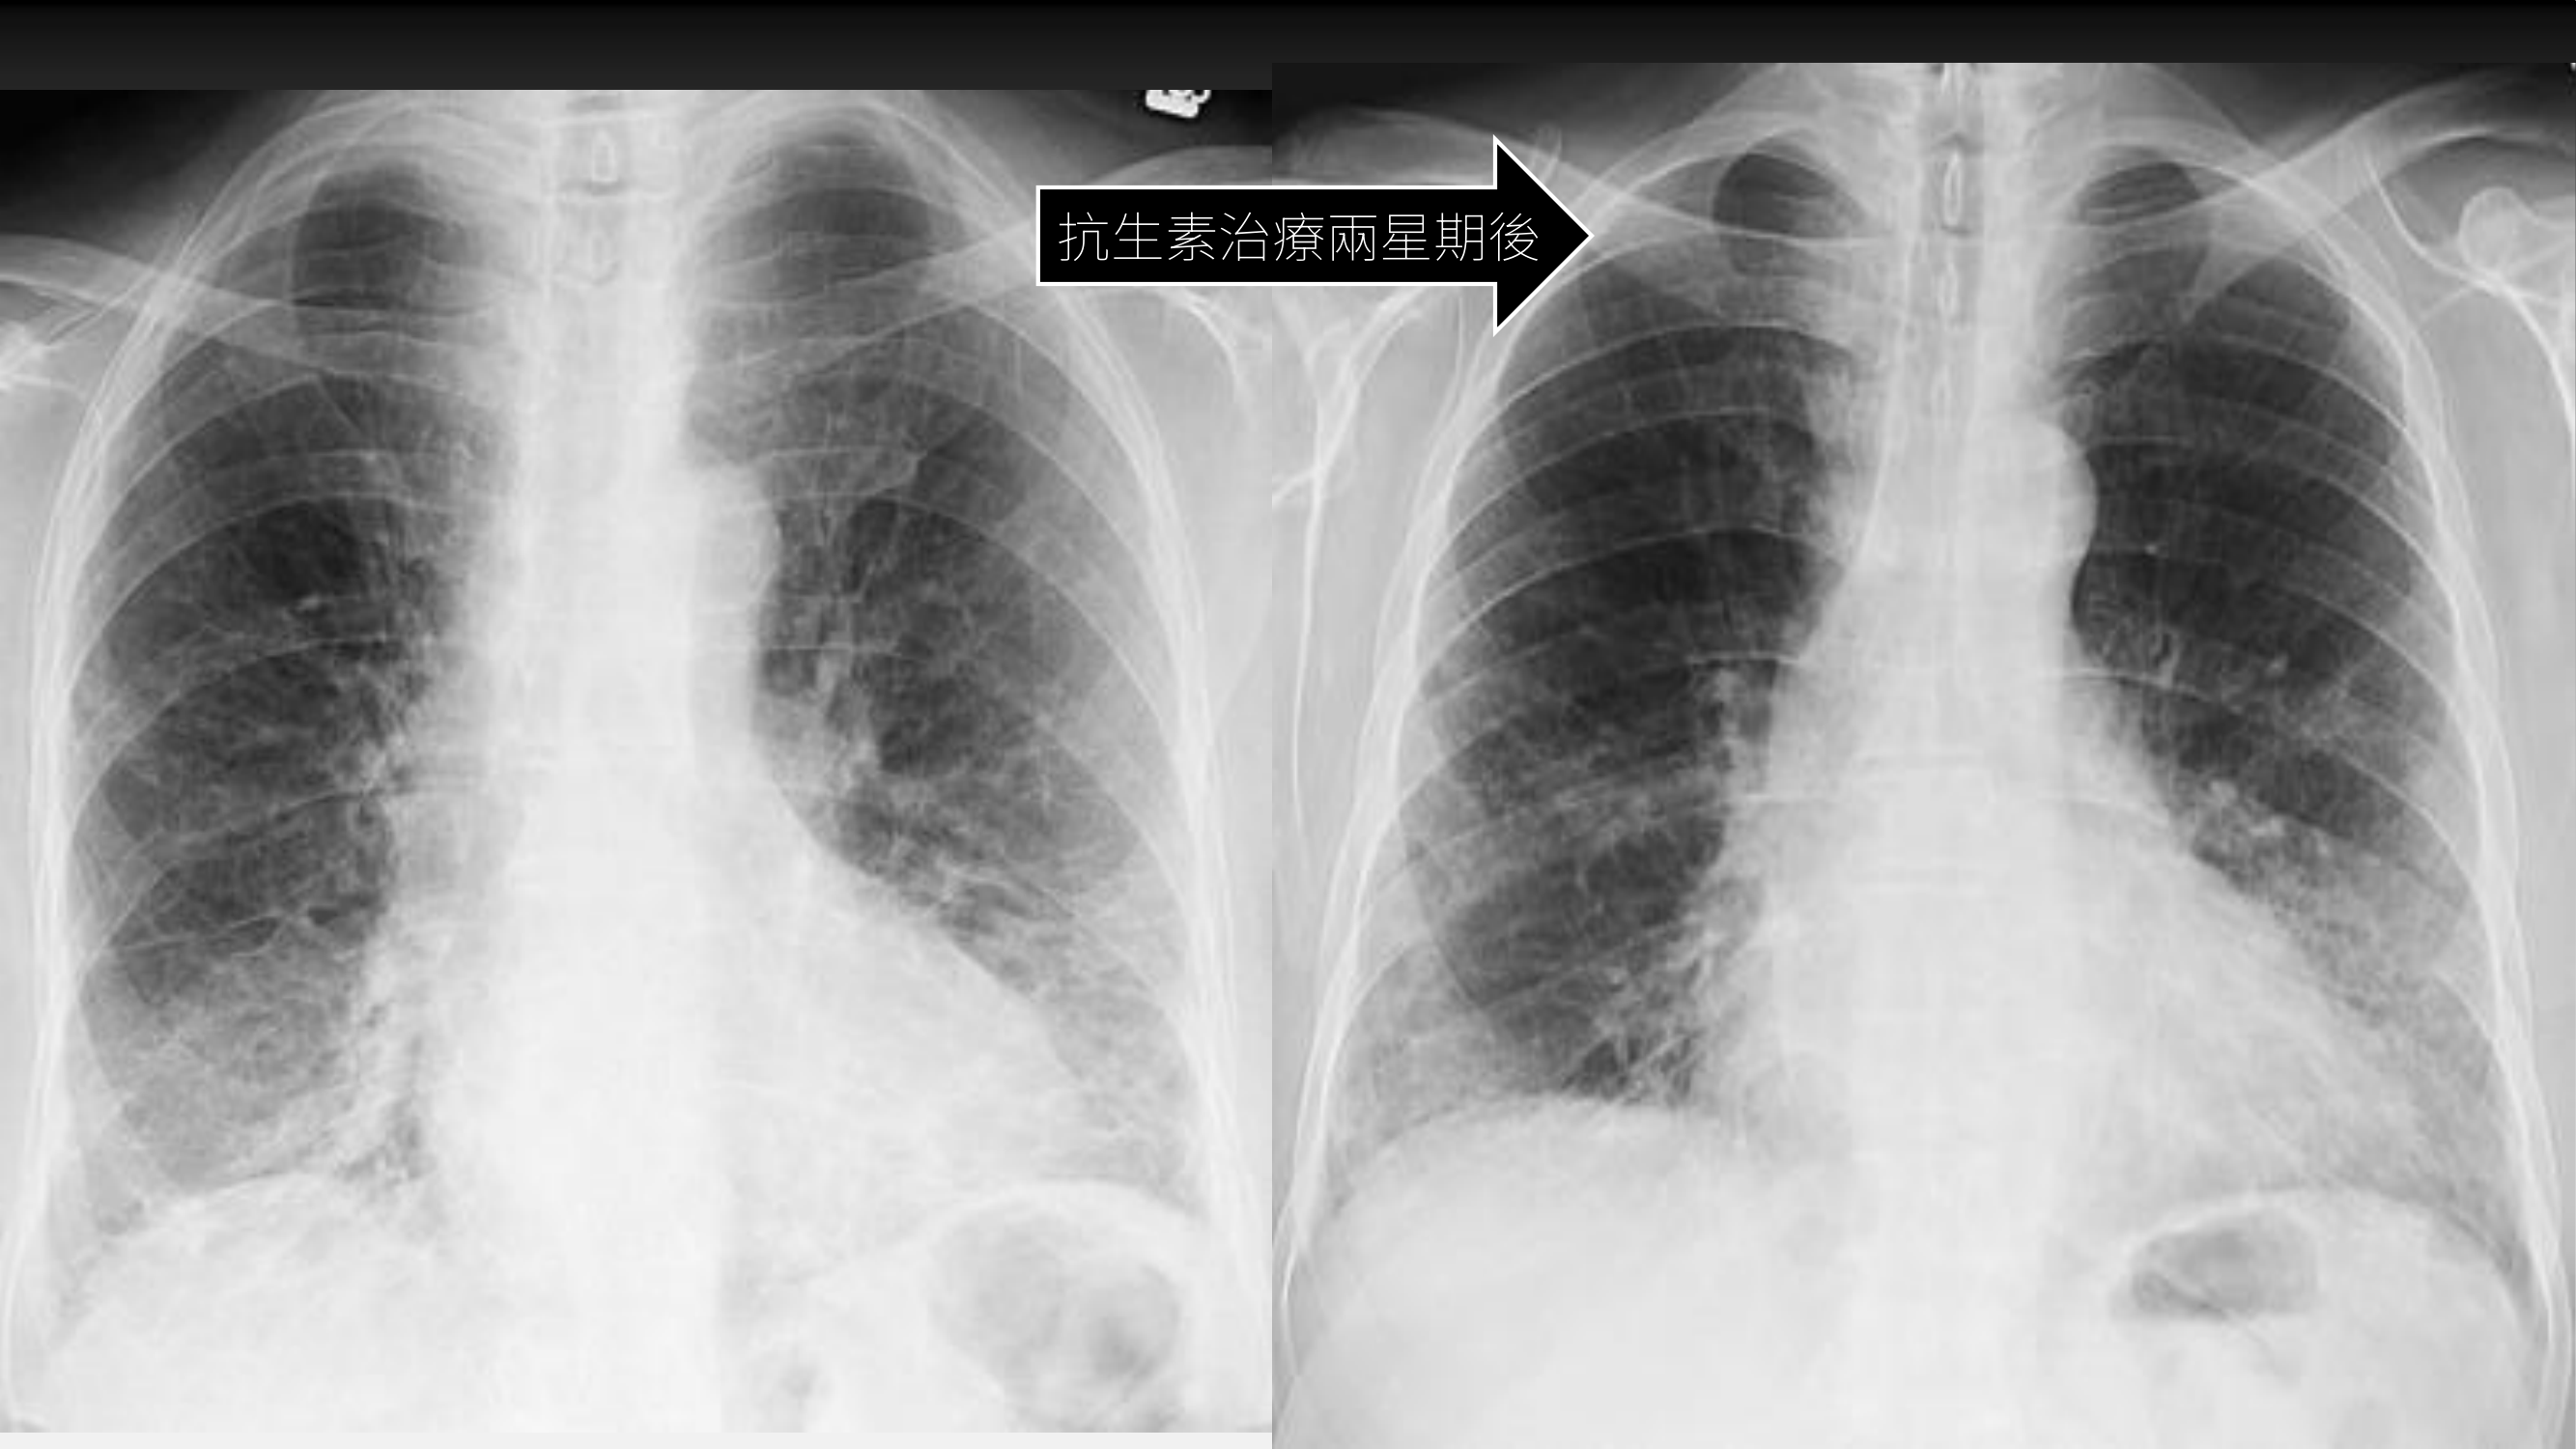

- 影像學判讀(CXR):

- 初步發現:雙側肺紋(Lung marking)增加。右肺中上肺葉紋理增粗至外 1/3,下肺葉出現類似 Foam wrap 的模糊影像。肋膈角(Costophrenic angle)尚清楚,心臟大小正常。

- Pattern 分析:呈現 Interstitial pattern(間質性變化),邊緣可見 Axial interstitial sign(類似 Curly line 的網狀紋理),以及支氣管血管束(Bronchovascular bundle)周圍的間質增厚,疊加部分 Ground glass opacity(毛玻璃狀病變)。

- 治療困境與最終診斷:

- 初期被誤以為肺炎,使用抗生素治療兩週後,影像局部進步但整體變化不大。

- 因缺乏感染徵兆(無發燒),僅以 DOE 為主,後續安排 HRCT。CT 顯示下肺有明顯纖維化(Fibrosis)、Ground glass 及 Interstitial 變化。